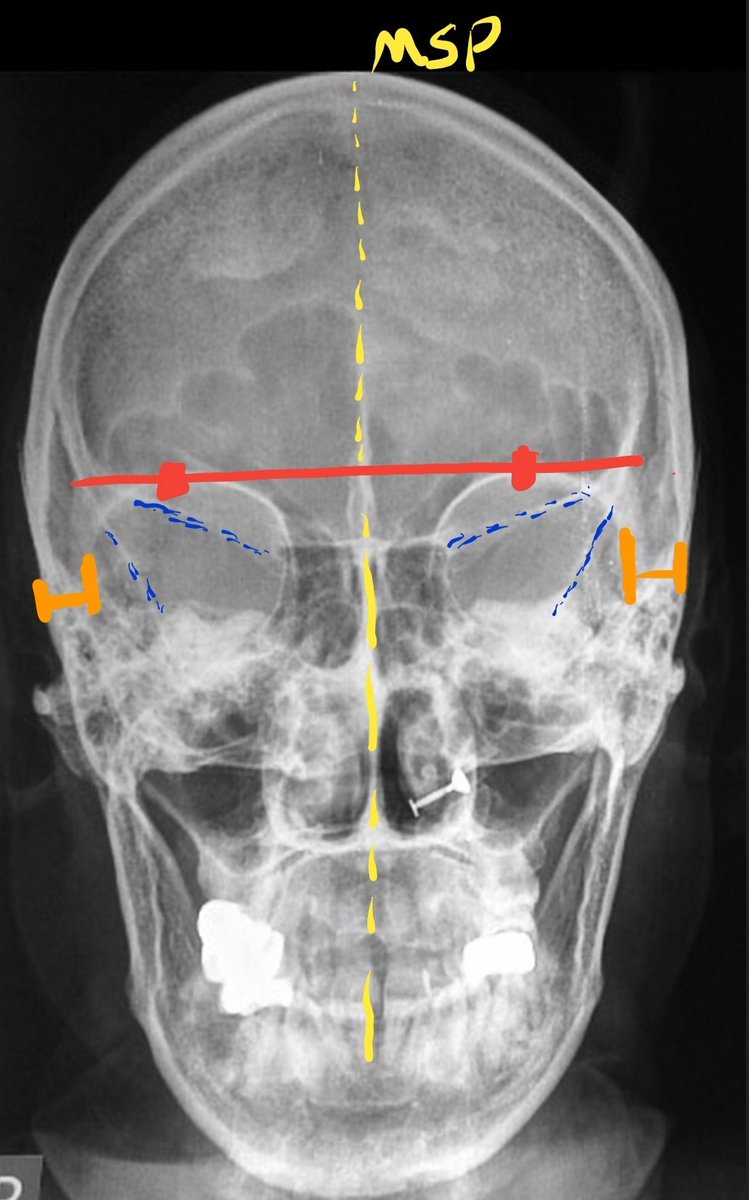

نقد الصورة والتأكد من تنفيذ الفحص بشكل صحيح:

١.لا بد أن تكون المسافة بين الحافتين الخارجية لمحجر العينين و الجدار الجانبي للجمجمة متساوية في اليمين و اليسار.(بالبرتقالي).

٢.تواجد

superior orbital fissures

بشكل متساوي داخل المحجرين(بالأزرق)

٣.لايوجد ميلان في MSP.